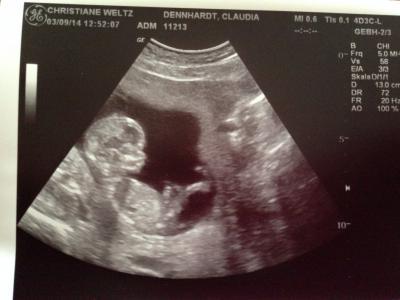

Hallo an alle werdenden März-Mamis , Wollte mich nun auch mal anschließen. Habe schon viele eurer posts verfolgt, aber bis jetzt war ich vorsichtig, ob mein kleiner Krümel auch bleibt. Jetzt habe ich genug Mut... Zu meiner Geschichte: Ich bin 29 Jahre jung und habe einen 7 jährigen Sohn. Ende 2013 war ich auch schon schwanger, jedoch wurden bei der Feindiagnostik Januar 2014 einige Auffälligkeiten bei dem kleinen Mann festgestellt, danach schloss sich eine Fruchtwasseruntersuchung an. Es war eine grausame Zeit, man hat sich alles schön geredet und trotz allem blieb die Ungewissheit und ein ungutes Bauchgefühl. Dieses bestätigte sich auch: Trisomie 18! aufgrund der z.T. Schwerwiegenden Organschäden und der sehr geringen Lebenserwartung dieser Kinder haben wir uns schweren Herzens für einen Abbruch entschieden. Am 1.2.2014 in der 22. ssw kam der kleine auf die Welt. Er war so perfekt...etwas später war die Beerdigung und wir konnten es damit besser verarbeiten. Die Trauer war unbeschreiblich. Naja und nach 3 Monaten Pause haben wir uns entschieden es erneut zu probieren und nun bin ich in der 14. ssw. Da ich Montag aufgrund der Vorbelastung das ersttrimesterscreening hab machen lassen und alles super in Ordnung ist, auch die Blutwerte, trau ich mich nun zu euch, um die Zeit mit anderen glücklichen Mamis zu teilen und zu genießen. Die Ungewissheit u Angst bleibt bei mir wohl immer aber ich möchte positiv denken. Eine lange Geschichte, sorry dafür. Gibt es bei euch auch Frauen die selbes Schicksal teilen?und wie läuft das mit der Kugelliste?hab mal ein aktuelles Ultraschallbild des kleinen Wunders dran gepackt. Ganz liebe Grüße

Das ist ja ein echt tolles Babybild, wirklich Wahnsinn!

Und WOW! Was für absolut perfektes Bildchen!

Wuuuunderschönes Bild